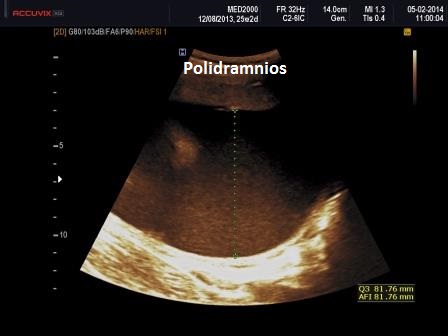

1. polidramnios (legato ai disturbi della deglutizione)